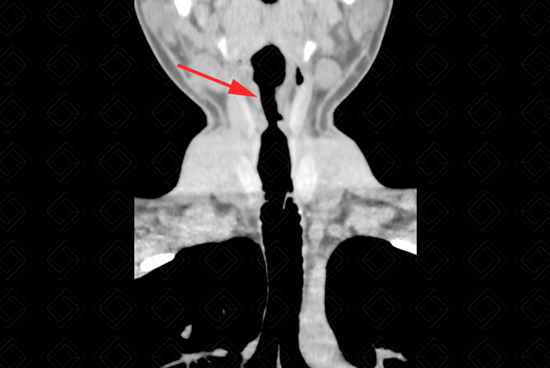

Texto alternativo para a imagem Créditos: Dra. Elazir Mota - Rio de Janeiro/RJ

Descrição da imagem: Redução do calibre traqueal de cerca de 50%, com grosseira irregularidade do contorno, localizado cerca de 3,5 cm abaixo da glote. [cms-watermark]

Exame de imagem: O exame de escolha para avaliação adequada diante da suspeita de estenose de traqueia é a tomografia computadorizada da região cervical e tórax. A tomografia também é excelente para excluir redução do calibre da traqueia por compressões extrínsecas. Na imagem, observamos evidente redução da luz da traqueia.